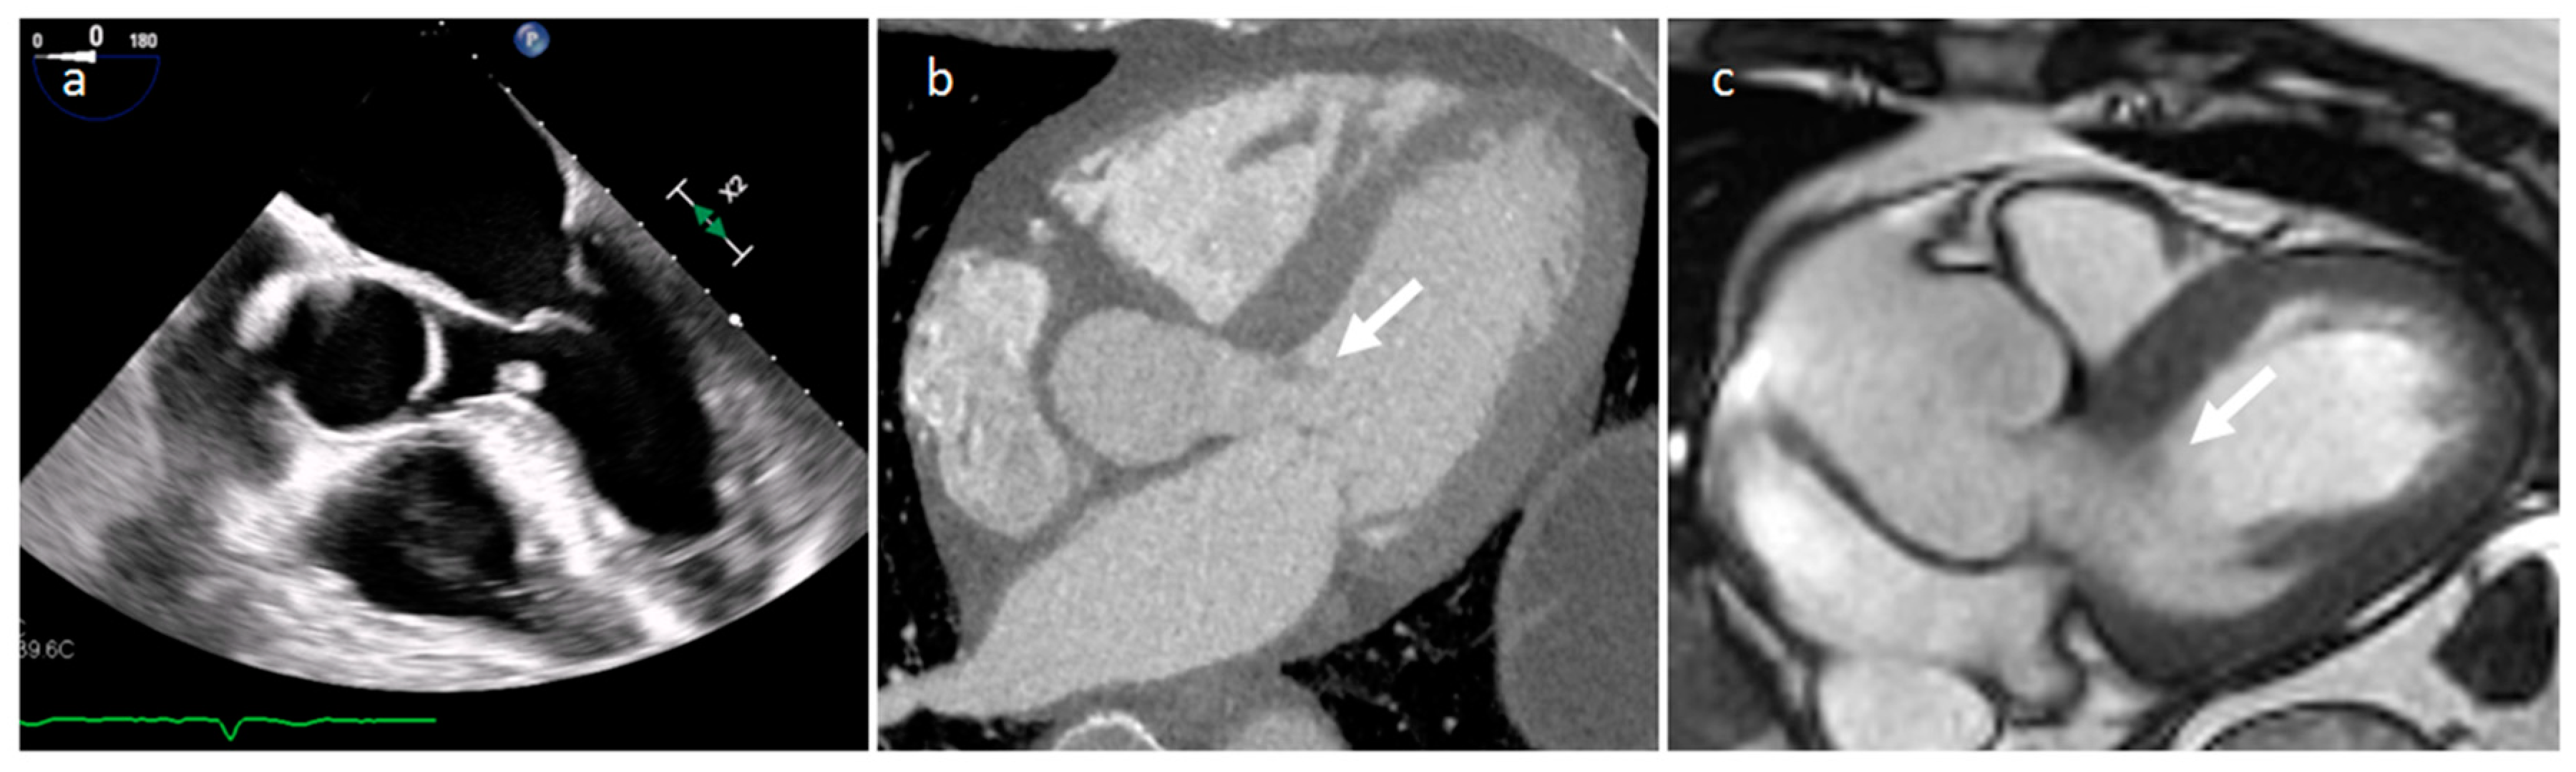

3.1. Thrombus

| Thrombus | Adulthood | LA, LAA (AF) LV (MI) | Asymptomatic, embolic events | Non-enhancing Intracardiac lesion | Acute: Low echodensity, rounded with smooth contours Chronic: High echodensity, linear or crescentic lesions along the endocardial surface | Low attenuation, no contrast enhancement, chronic thrombus may be calcified Usefulness of delayed CT imaging, as in the LAA stasis of blood can simulate a thrombus on early arterial images | Acute: hyper T1w and T2w Subacute: hyper T1w and hypo T2w Chronic: low T1w and T2w No enhancement. |